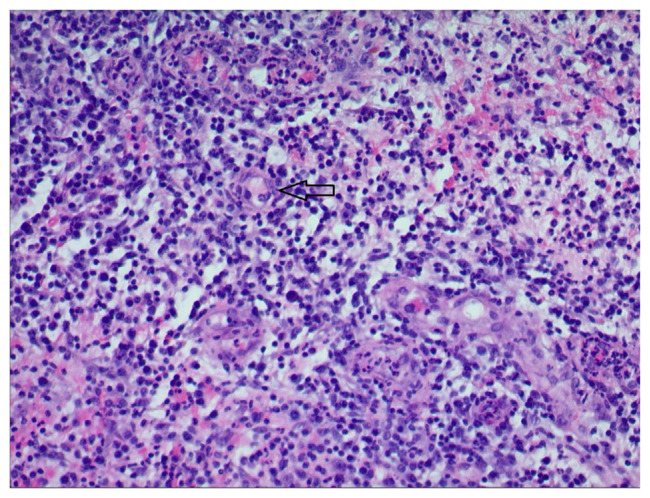

Levamisole-induced vasculitis is a recognized dermatopathologic phenomenon frequently observed in individuals engaged in illicit substance use, particularly cocaine. Levimasole's structural resemblance to cocaine leads to its utilization as a cutting or bulking agent, creating an illusion of unaltered purity. While this vasculitis typically manifests in cartilaginous areas such as the ears and nose, it can also occur, though less commonly, in the lower extremities. At the time of writing, our case is the 3rd case of levamisole induced vasculitis to affect the lower extremities. The primary therapeutic approach involves discontinuing the use of the implicated agent, as repeated exposure to levamisole tends to exacerbate skin lesions with subsequent use. In this report, we present the case of a 30-year-old female with a history of cocaine use, who presented with extensive bilateral chronic leg wounds affecting her ambulation. Histopathological analysis of the skin biopsy confirmed signs of levamisole-induced vasculitis. Our objective is to raise awareness among both the public and healthcare providers, emphasizing the consideration of cocaine-induced vasculitis in patients presenting with chronic non-healing wounds, even in less common anatomical regions. Encouraging substance use cessation is crucial in the management of such cases.